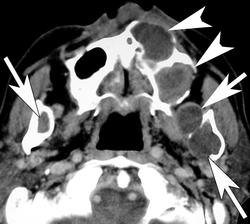

Гольца (Гольтца) (Goltz) - Горлина (Gorlin) синдром.

Наследственная болезнь, проявляющаяся образованием резко отграниченных очагов истонченной гиперпигментированной кожи, дистрофией ногтей, гипотрихозом (слабо развитым оволосенением), аномалиями развития глаз, гортани, сердца, скелета.

Рентгенологическая картина

Горлина - Гольца синдром

http://radiopaedia.org/articles/gorlin-goltz-syndrome-1

http://radiopaedia.org/images/32209